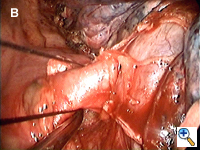

Dissecting around a pulmonary vessel is basically the same as in conventional, open surgery. We use a right-angle Mixter clamp to go around a vessel, and then loop it with a heavy silk ligature. With gentle traction on the suture, a dental pledget is used to gently dissect the undersurface of the vessel. A mechanical stapler (Endo-GIA 30V; Autosuture, United States Surgical, Norwalk, CT) is then introduced through one of the other two ports (depending on the alignment), but usually the camera port (with the thoracoscope repositioned to view through the minithoracotomy wound) to staple-transect the vessel. Appropriate traction (using a sponge holding forceps from the other port) is crucial in aligning the vessel with the stapler for transection (Figure 3). In recent years, we have been using more frequently ligation of pulmonary arterial branches with extracorporeal knots instead of mechanical staplers mainly to reduce cost.[5] We tend not to use many endoclips for small pulmonary branches, as their presence could interfere with the subsequent use and functioning of the endostaplers.